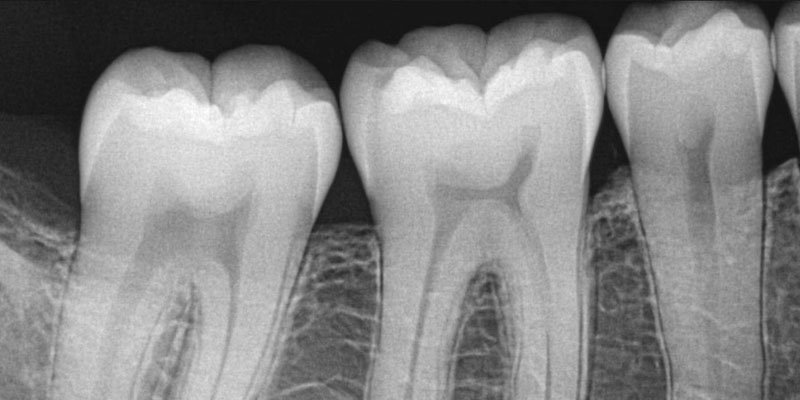

The majority of your teeth, along with the support structure that prevents them from falling out, is about 12 mm BELOW your gums. While we strive to keep those pearly whites sparkling and clean on the outside, it is also our duty to make sure your teeth not only look good, but are healthy and disease free.

Dental x-rays allow us to have a complete visual of your teeth and the bone that surrounds them. We are able to detect infections and disease that may be occurring deep within your jaw; tumors that may have developed within your bone, or cracks that have traveled from the top of the tooth all the way to the root. X-rays give us important information that we are able to use to plan ahead, prevent future complications, and put together a treatment plan that is catered to you.